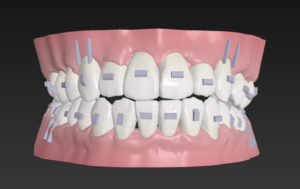

この歯並びが治る原理は

歯と歯の間を0.2から0.6ミリ削る

IPRという医療行為を行い

スキマをつくり

これを利用して歯をキレイに整列

🔶アフター🔶

正面

右

左